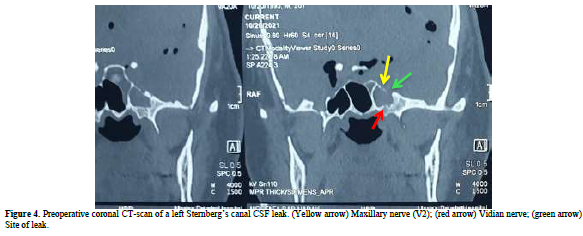

A computed tomography (CT) scan revealed a defect in the middle cranial fossa communicated to the lateral recess of the left Sphenoid Sinus and a soft tissue density within the sinus, with air void signal extended in to the left temporoparietal and frontal hemisphere (Figures 1-4). It appeared to be due to persistence of the Sternberg’s canal.

The patient underwent endoscopic endonasal trans-sphenoidal approach surgery by a Neurorhinologist/ Endoscopic Skull base surgeon. The bony defect in the Left SS lateral recess was identified during the procedure and the protruded meningencephaloocele (Figure 5) was reduced in volume by bipolar cauterization and the defect was filled with bone of middle turbinate, fat and fascia lata from anterolateral aspect of thigh.